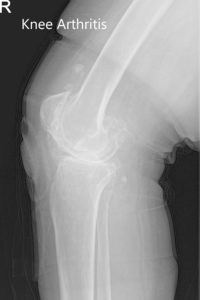

Sus estudios de imagen revelaron osteoartritis tricompartimental severa de la articulación bilateral de la rodilla. Después de una cuidadosa consideración de sus condiciones y necesidades médicas, se le aconsejó un reemplazo total de rodilla personalizado bilateral. Se le hizo consciente del mayor riesgo asociado con la cirugía bilateral. Las alternativas, los riesgos y los beneficios se discutieron en detalle con él y su hijo. Estuvieron de acuerdo con el procedimiento.

Radiografía preoperatoria de la rodilla izquierda que muestra AP y vistas laterales.

Radiografía preoperatoria de la rodilla derecha que muestra AP y vistas laterales.